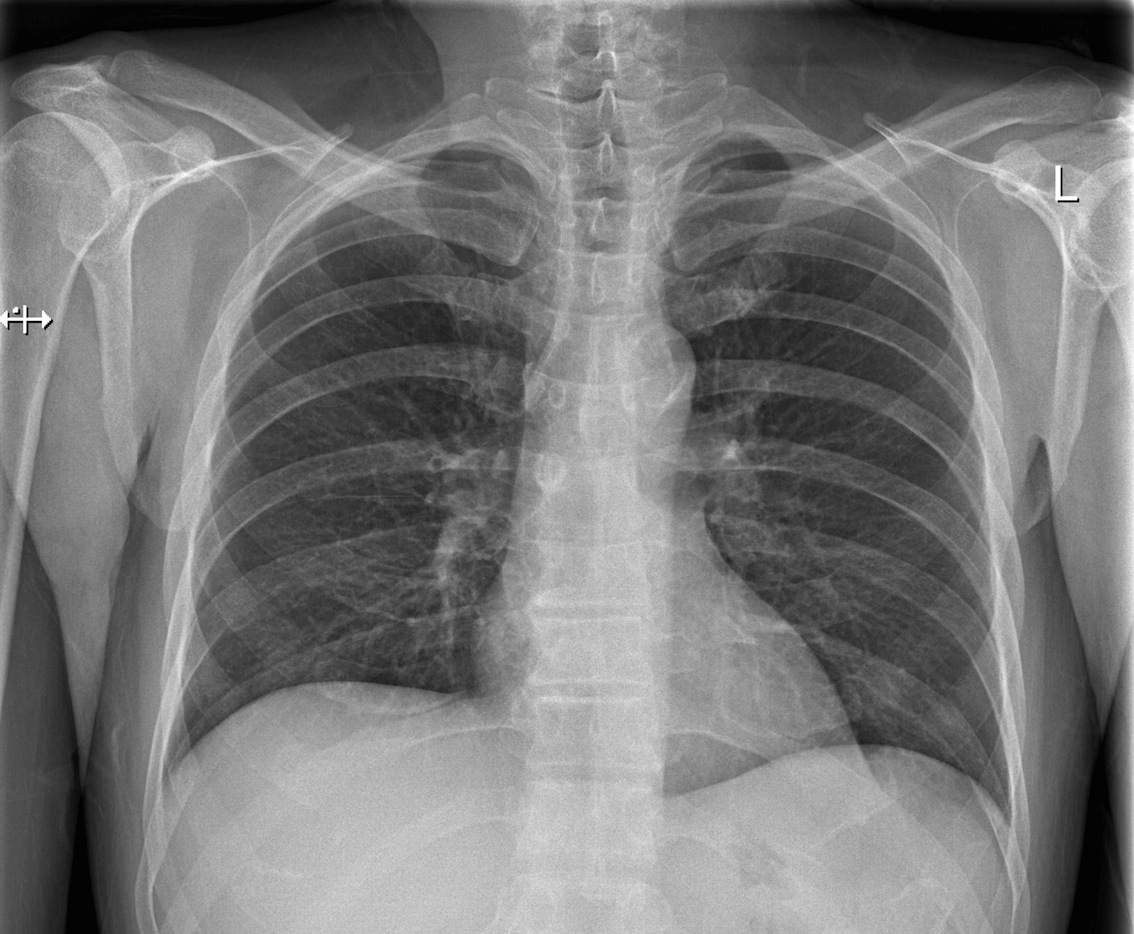

PACS is the radiology world's digital storage and distribution system for radiology imaging. While most countries in the wetsern world are now entirely digital in their radiology imaging, this was emphatically the case in the UK by 2009 thanks in part to the National Programme.

In the UK, we have records of radiology procedures dating back for 10, 15 more years. These are really full records. Digital images in a format that is rich in analyzable data and easily correlated with the radiologists' reports. This is an absolute dream for any machine learning algorithm. The same is true in many Western countries, but there is an added NHS benefit. The radiology data practices in the NHS are, relatively speaking fairly well standardised. There are standard terminologies and classifications. Of course there are variations, but on the whole the way one radiology department describes its data is very much the same as any other across the UK.

This is so ripe for machine learning. Image analysis tools paired up with report data and further, we even have vast amounts of outcomes data for patients that could be correlated.

Here is the key: we already have a huge set of radiology images with known classified outcomes. The training dataset is enormous! Most often, it is the gathering of the training data that is the hardest step. In radiology, the image space is bounded (we don't have random pictures of cars to throw out), the format of the data is high quality and we have correlated reports (and outcomes).